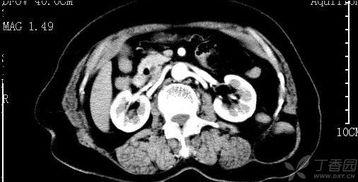

最近腰酸背痛的,是不是你也和我一样,感觉腰杆子都快弯成虾米了?别急,今天就来给你揭秘一下腰椎CT视频的奥秘,让你对自己的腰杆子有个更清楚的了解。一、腰椎CT视频...